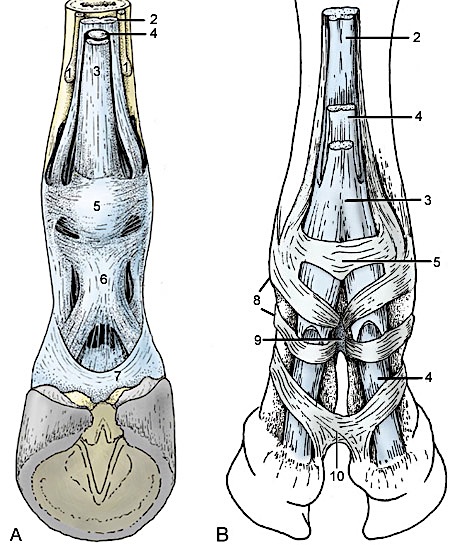

www.horseforum.comAnnular Ligament Stock Photos & Annular Ligament Stock Images - Alamy

www.horseforum.comAnnular Ligament Stock Photos & Annular Ligament Stock Images - Alamy

www.alamy.comligament annular flexor superficial stock anatomy alamy distal digital domestic veterinary animals tendon

www.alamy.comligament annular flexor superficial stock anatomy alamy distal digital domestic veterinary animals tendon

Annular Ligaments In The Horse Forelimb Diagram | Quizlet